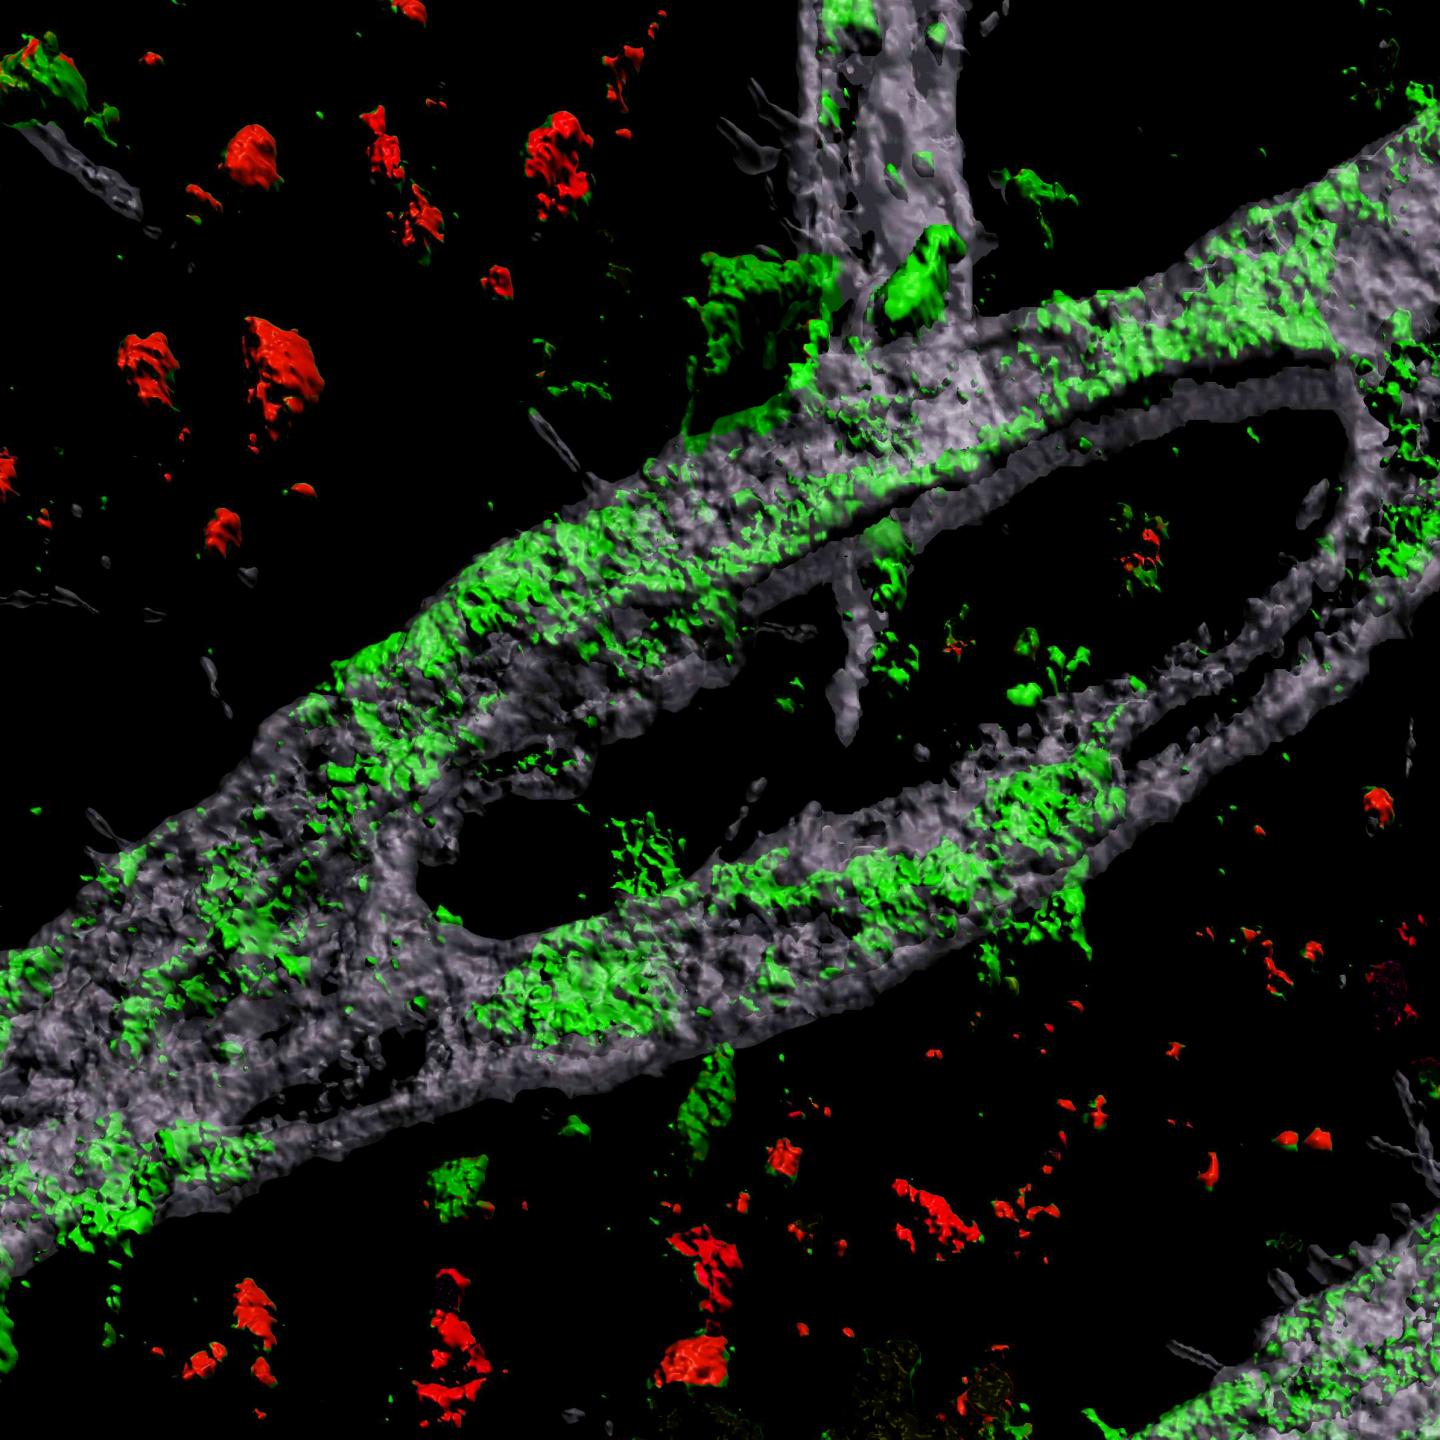

image: A 3D rendering of a lab-grown blood brain barrier carrying the APOE4 gene variant shows a heavy accumulation of amyloid on the vessel (green).

Blanchard et. al./MIT Picower Institute

Grown for two weeks within a three-dimensional hydrogel scaffold, the BBB model cells assembled into vessels that exhibited natural BBB properties, including low permeability to molecules and expression of the same key genes, proteins and molecular pumps as natural BBBs. When immersed in culture media high in amyloid proteins, mimicking conditions in Alzheimer's disease brains, the lab-grown BBB models exhibited the same kind of amyloid accumulation seen in human disease.

With a model BBB established, they then sought to test the difference APOE4 makes. They showed by several measures that APOE4-carrying BBB models accumulated more amyloid from culture media than those carrying APOE3, the more typical and healthy variant.